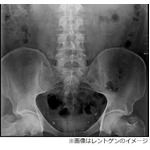

手術で“健康な睾丸”を誤摘出、「父親になれない」と病院を提訴。